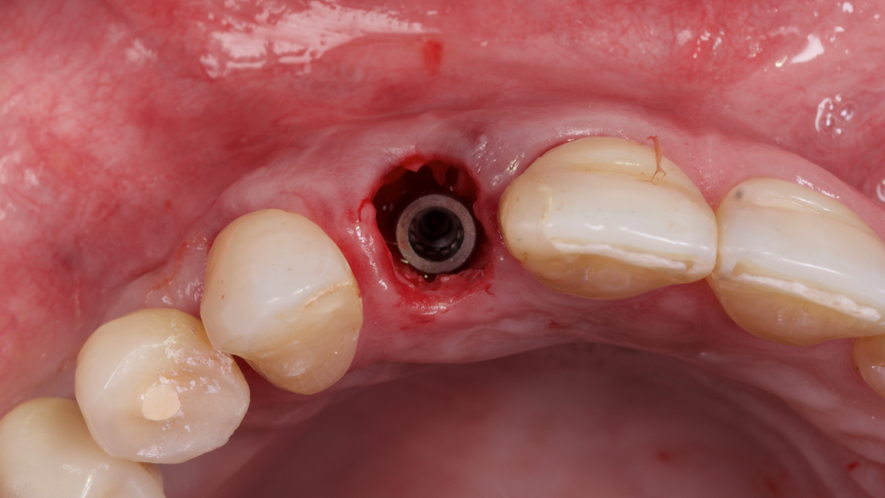

Este trabalho tem como objetivo relatar um caso clínico de exodontia minimamente invasiva de um incisivo lateral superior com fratura radicular, realizando implante imediato em alvéolo pós-extração, enxerto de tecido conjuntivo subepitelial e osso bovino liofilizado para preenchimento de GAP, prontamente à instalação de pilar reto e provisório imediato.